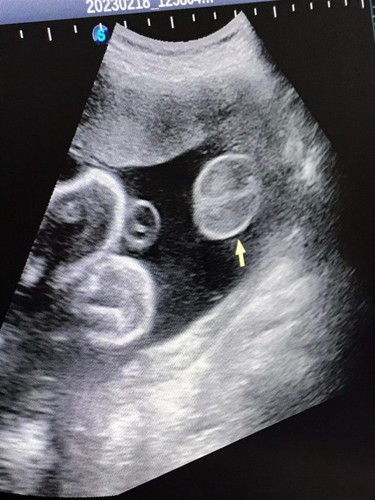

แบบนี้ผู้หญิงหรือผู้ชายค่ะแม่ๆ #ขอบคุณล่วงหน้านะคะ #คุณแม่ๆช่วยแนะนำหน่อยค่ะ

ไข่ชัดขนาดนี้แม่คิดว่าผู้หญิงไหมล่ะค่ะ🤣🤣

ผู้ชายค่ะ จากประสบการณ์ ไข่กลมขนาดนี้😅

มาเป็นพวงเหมือนลูกชายบ้านนี้เลยค่ะ😆

น่าจะมีหนอนน้อยเหมือนบ้านนี้นะคะ😂

ใครมองเป็นใข่ แต่เรามองเป็นกลีบค่ะ 😂

ผู้ชายจ้า บ้านนี้ก็โชว์ไข่จ้า555

ไข่มาเป็นพวงเลยค่ะแม่